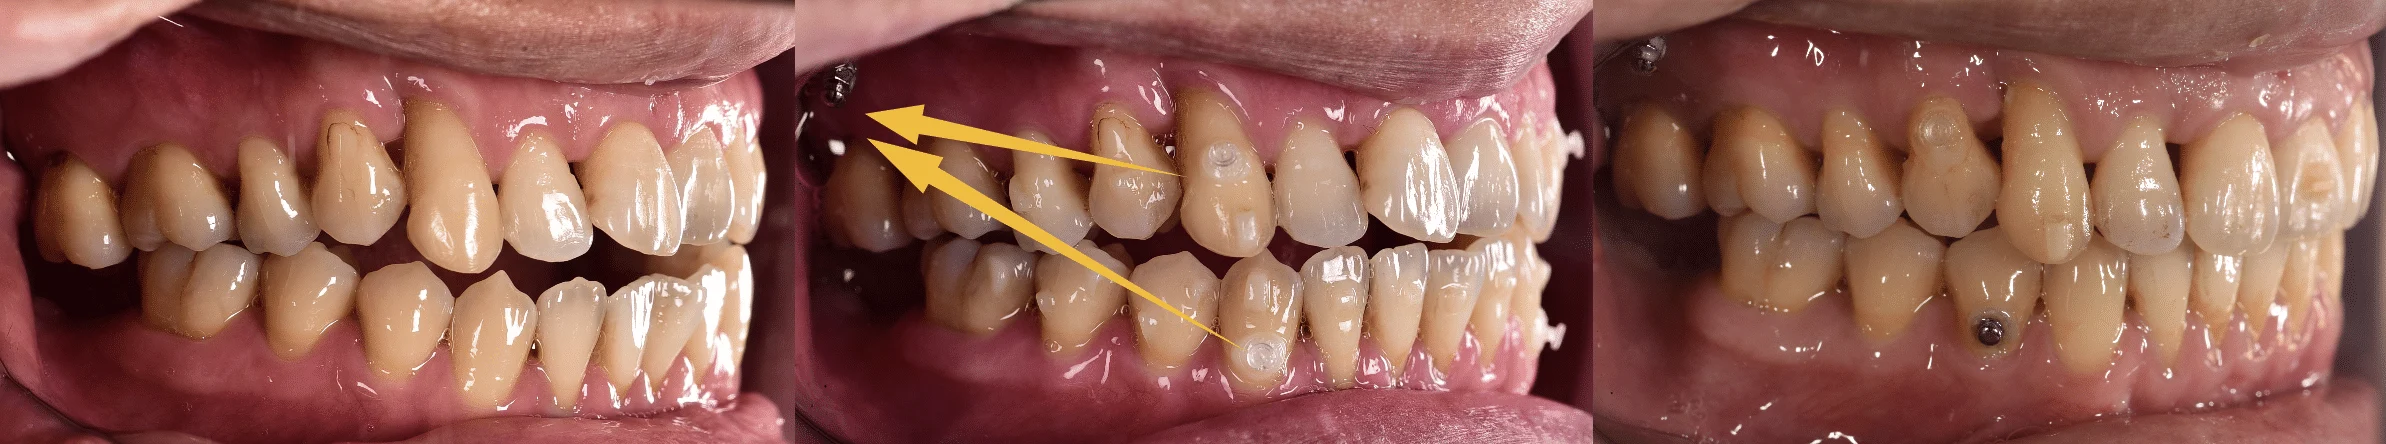

黃⾊箭頭指的是從牙⿒拉橡⽪筋到骨釘

矯正期間:1年6個⽉

開咬指的是上下前牙無法接觸,最常聽到的抱怨就是麵咬不斷,⼤部分案例

需要透過拔牙才有辦法改善開咬,此案例透過隱適美與骨釘將上下前牙向內

退縮,除了排⿑牙⿒亦能改善開咬!